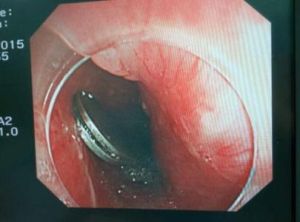

胃內異物2.纖維內鏡檢查 由於纖維內鏡檢查已廣泛套用於臨床,因此只要異物吞入時未造成食管損傷或嵌頓者,無論是金屬性或非金屬性異物均可採用纖維內鏡檢查。尤其是X 線不能顯示的非金屬異物,凡有可靠的異物吞入史便應常規纖維內鏡檢查,以免延誤診治時機有些患者雖有確切的異物吞服史,但無X 線和纖維內鏡檢查設備,病人又無明顯症狀體徵出現,可密切觀察,並仔細檢查大便有否異物排出。如果5~7 天仍無異物排出,患者有明顯的腹部症狀體徵出現,應及時轉至上級醫院進一步檢查以明確診斷。